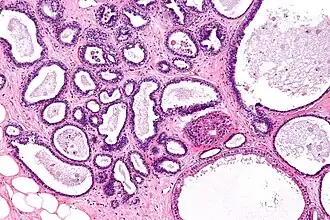

Histologie de la mastopathie kystique diffuse

La mastose ou mastopathie kystique diffuse est un terme qui englobe un certain nombre de lésions histologiques bénignes non cancéreuses et non inflammatoires.

La mastopathie kystique diffuse se caractérise par l'apparition, dans les deux seins, de formations kystiques régulières, sans attache avec le tissu sous-jacent.

Le nombre de kystes développés dans un sein peut être minime (1 ou 2) mais il est souvent élevé (plusieurs dizaines). Il réalise alors avec la fibrose adjacente des placards palpables et sensibles, d'allure clinique parfois ambiguë : il peut être difficile de les différencier d'un cancer[4].